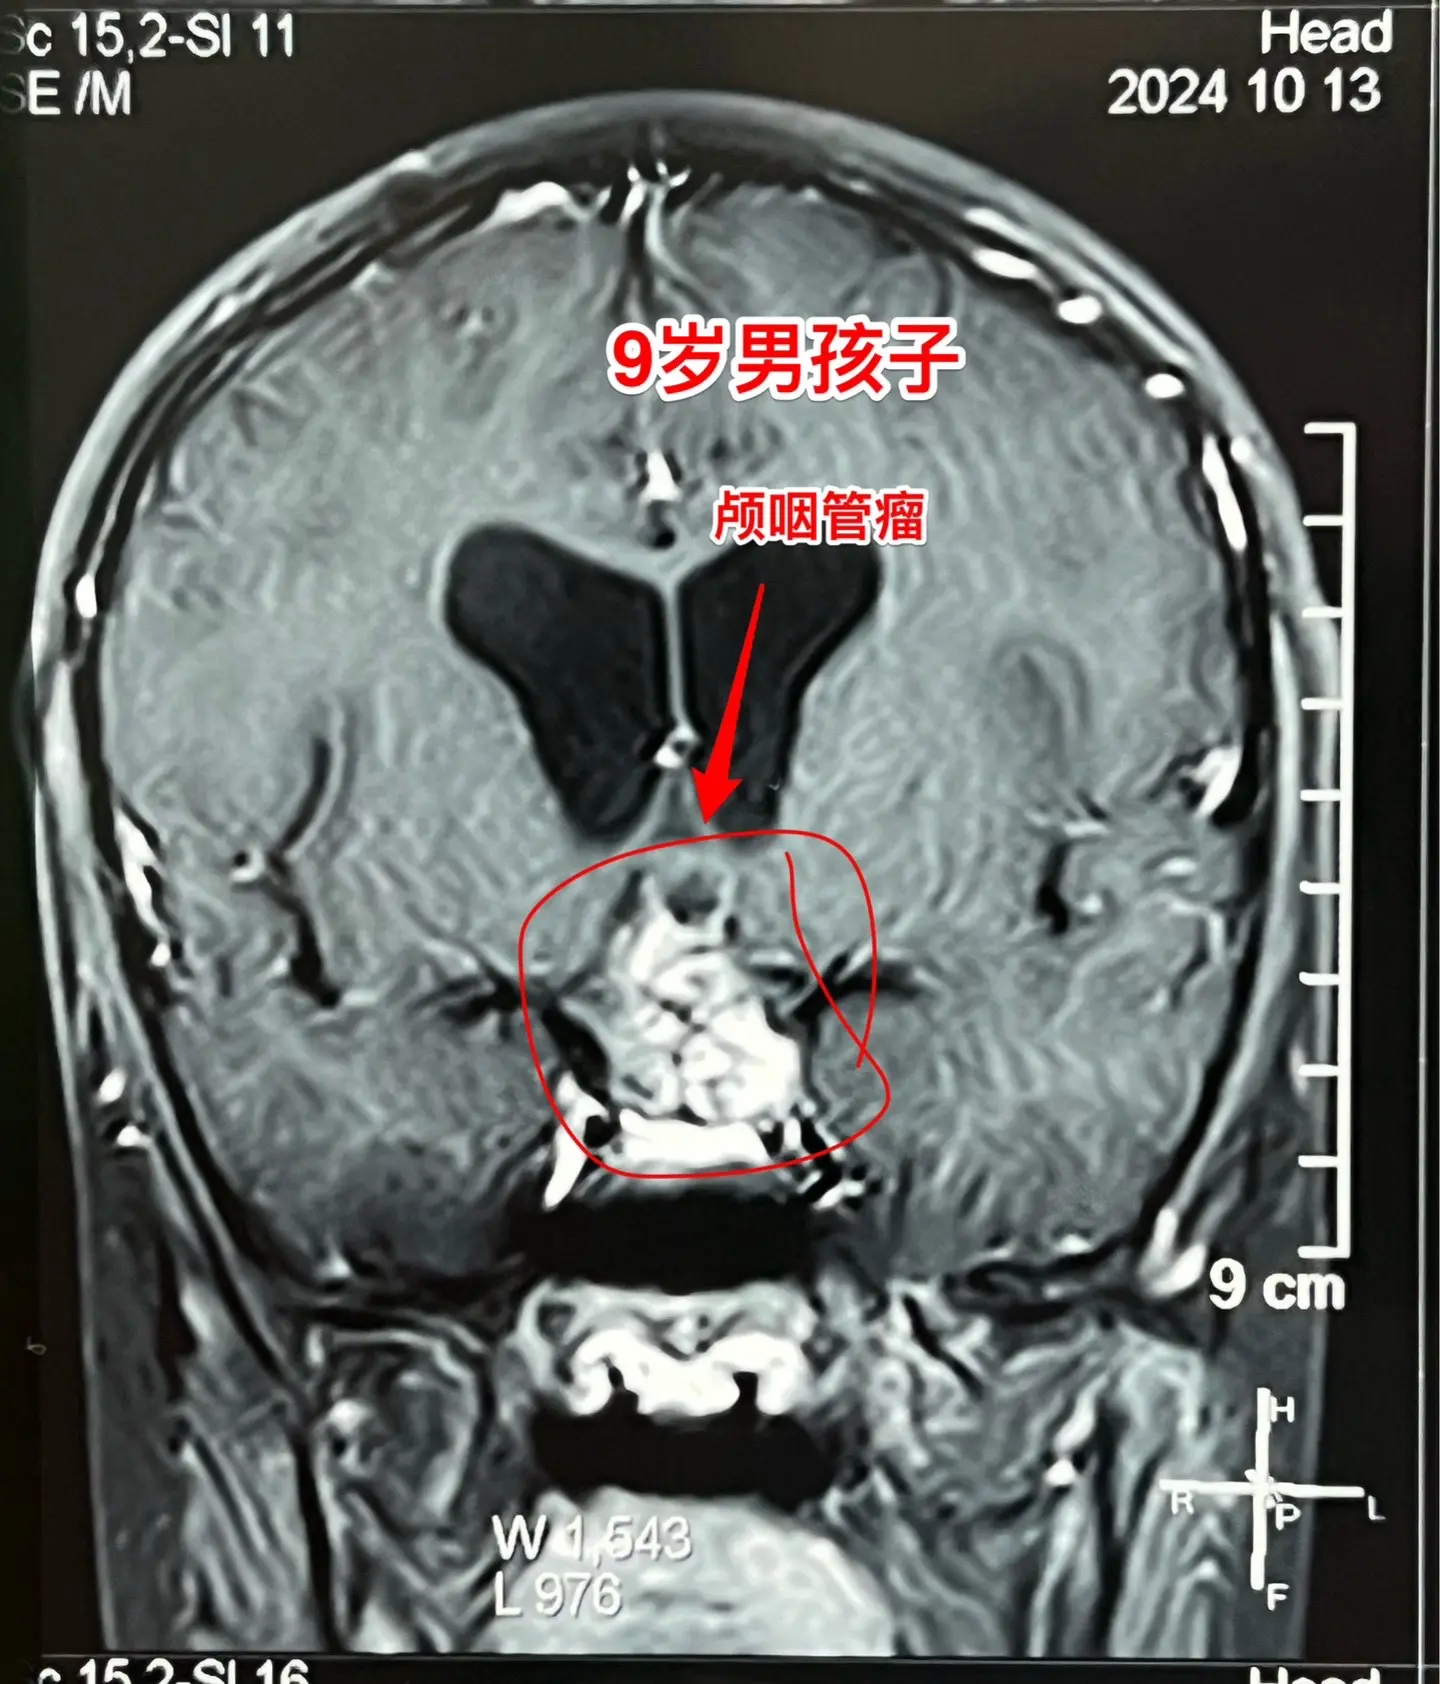

今日两个颅咽管瘤手术。1,6岁男孩子,安徽宿州人。2023年5月因视力下降发现了脑部长了巨大颅咽管瘤,见图1。家长曾经通过微信找我看过,最终选择在上海某医院行手术治疗,手术后出现右侧偏瘫,经过康复治疗后能勉强走路,但是右手还不能拿笔写字。2023.12磁共振就显示颅咽管瘤复发了(多块肿瘤复发)。2024.10又出现视力下降,故来找我作手术。今天手术中发现有四块较大的肿瘤,同时有很多个小钙化。所见肿瘤均顺利切除了。对比两次手术前的磁共振,可以说第一次手术更容易达到完全切除肿瘤,很遗憾,那一次机会错过了。 2,9岁男孩子,江苏盐城市的。因头痛、呕吐检查发现脑部有典型的颅咽管瘤,伴有脑积水。病人到我科住院后经用甘露醇和地塞米松后头痛、呕吐症状消失,能正常吃喝。今日作了开颅手术,顺利切除肿瘤。